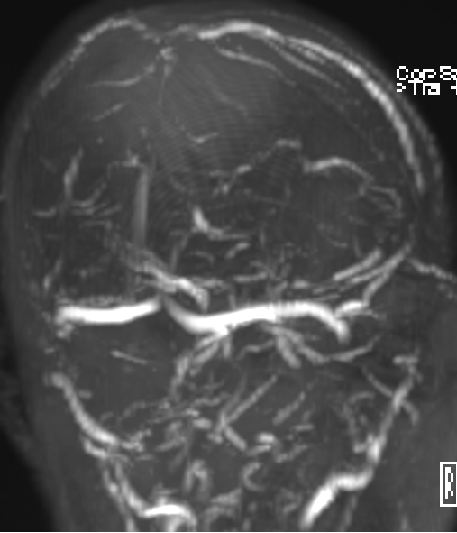

2013-8-2 MRI

2013-8-2 CT

腰穿脑压240